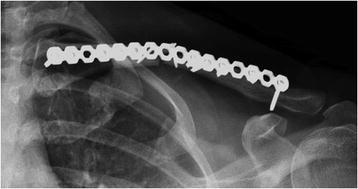

Does plate type influence the clinical outcomes and implant removal in midclavicular fractures fixed with 2.7-mm anteroinferior plates? A retrospective cohort study.

Anteroinferior clavicular fracture fixation with 2.7-mm dynamic compression plates results in excellent healing rates with low removal rates in accordance with the published literature. Given higher rates of failure, 2.7-mm reconstruction plates should be discouraged in comparison to stiffer and more reliable 2.7-mm dynamic compression plates.